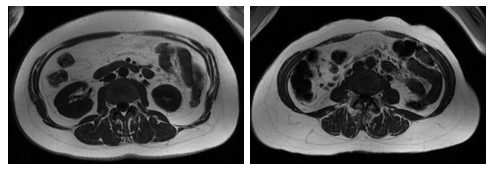

weight and waist circumference can show largely different amounts

of visceral fat vs. fat under the skin in the abdomen